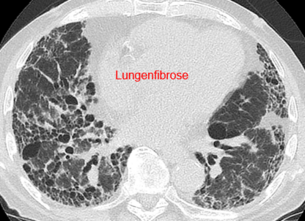

Interstitielle Lungenerkrankungen (ILD) – HRCT und Einordnung im Team

Interstitielle Lungenerkrankungen (ILD) sind Erkrankungen, bei denen sich das Lungengewebe durch Entzündung oder Vernarbung verändert. Die High-Resolution-Computertomographie (HRCT) ist dabei ein zentrales Werkzeug, weil typische Muster in der Bildgebung wichtige Hinweise auf Ursache und Stadium geben.

Beispielhafte Aufnahmen verschiedener Erkrankungen

(Lungenklinik Lostau)